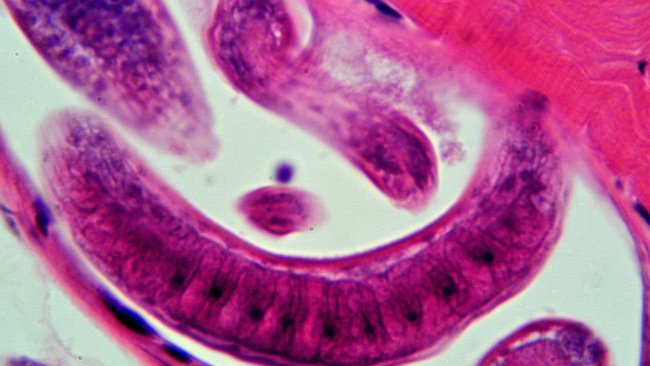

La detección de personas infectadas por triquinosis ha llevado al SENASA al sacrificio controlado de animales de 3 granjas de la província de Córdoba.